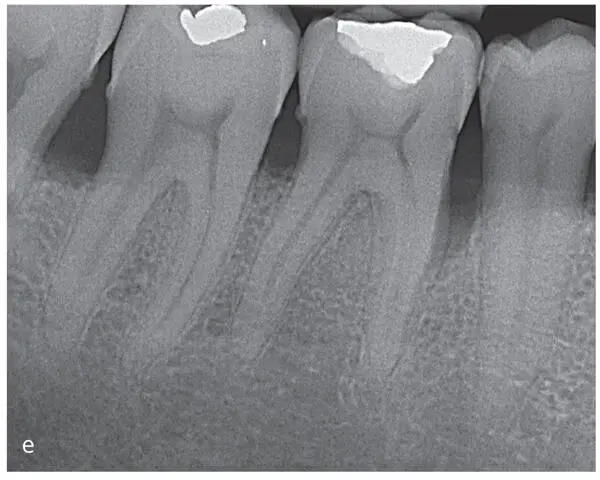

Figs 2-9a to fRadiographic images of the therapeutic outcome 2 years after regenerative surgical therapy. (a) Baseline radiograph: maxillary right second premolar to third molar. (b) Radiograph 2 years after surgery: maxillary right second premolar to second molar, with radiographic bone fill indicating periodontal regeneration upon application of enamel matrix derivatives. (c) Baseline radiograph: maxillary right second premolar to second molar. (d) Radiograph 2 years after surgery: maxillary right second premolar to second molar. (e) Baseline radiograph: mandibular right second premolar to second molar. (f) Radiograph 2 years after surgery: mandibular right second premolar to second molar, with radiographic bone fill indicating periodontal regeneration upon application of enamel matrix derivatives.